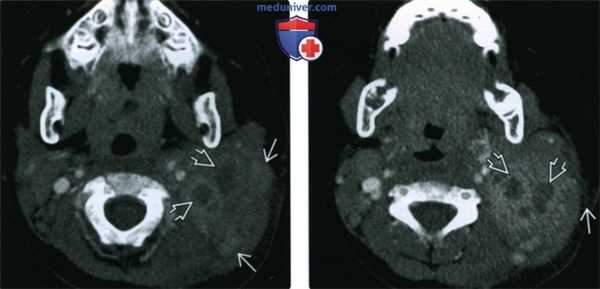

(Слева) КТ с КУ, аксиальная проекция, ребенок. Конгломерат, захватывающий несколько пространств верхнего отдела шеи, с участками пониженной плотности, характерными для нагноения. В толще конгломерата также имеются солидные, реактивные лимфоузлы.

(Справа) КТ с КУ, срез на более низком уровне, этот же пациент. В конгломерате лимфатических узлов имеются очаги нагноения. Исчерченность жировой клетчатки, расположенной кнаружи от образования, говорит об инфекционной природе процесса. При аспирации был выявлен причинный микроорганизм - Staphylococcus aureus.